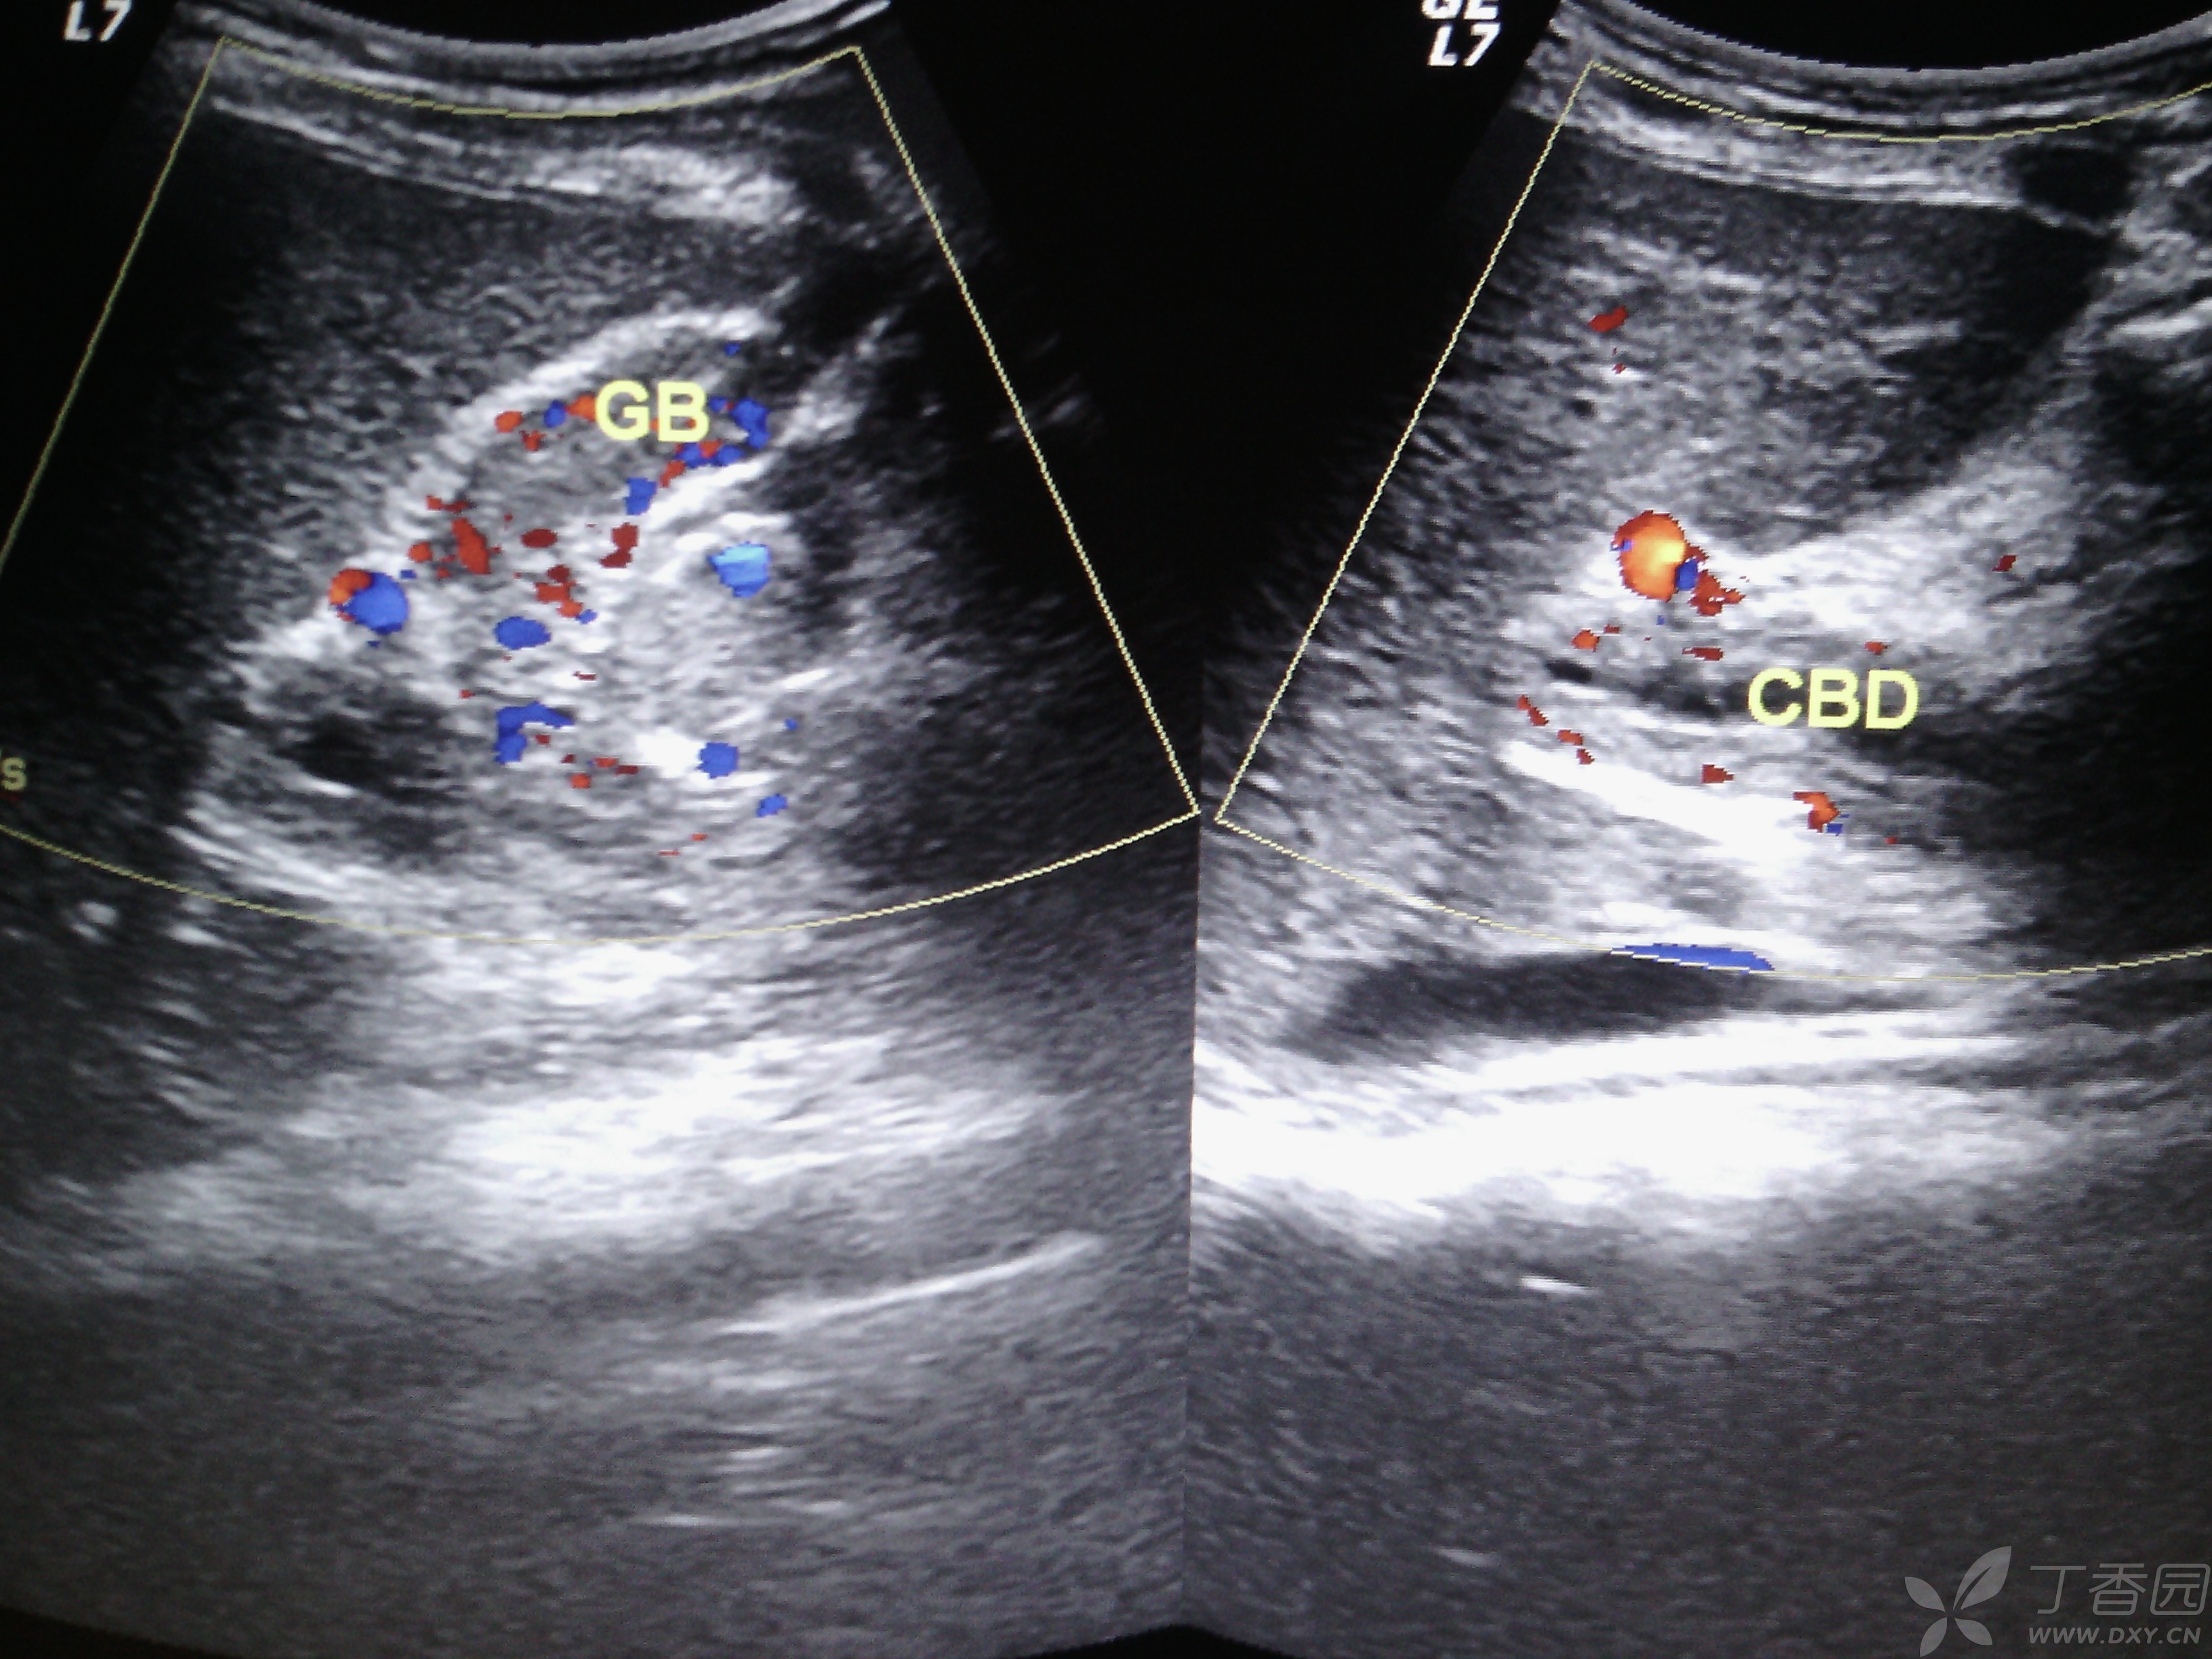

1、祝好点击这里查看我的门诊时间 北大医院张骞大夫郑重提醒因不能面诊患者,无法全面了解病情,以上建议仅供参考,具体诊疗请一定到医院在医生指导下进行参考资料北大医院张骞彩超中GB;办理病退的条件一是,丧失劳动能力,到指定医院鉴定二是,年龄男性满50周岁,女性可能是45周岁由本人提出申请关于退休待遇,养老金缴费必须满15年,可享受养老金待遇,拿多少养老金,按缴费年限和多少而定,不存在按80%或60%算这一说三是,关于医疗保险待遇,男性必须缴满30年,女性必须缴满。

2、1我厂在技术设计中,优化设计,精益求精,与设计院贵公司密切合作,保证设计工作的顺利开展,并积极听取4我方所供设备产品,其性能符合中国制定的G *** 282097柴油发电机组标准及ISO8528国际标准1 彩超室患者检查结束即时出具报告,CT及普放患者急诊半小时出具报告,平诊两小时出具报告,疑难病例两日彩超中GB;结合全新的技术平台,保证更佳图像性能的完美呈现高性能豪华型全数字主机高亮度高分辨率彩色医用液晶显示器高灵敏度超大触摸屏,让医生在临床应用中享受更多的操作乐趣最新计算机平台设计采用最新的Windows操作系统,功能更丰富,性能更稳定 采用PIV30GHz的双系统CPU,560Gb的系统硬盘,知您所需;对,多躺着别乱活动, *** 口开了害怕彩超中GB你流产 cn#GVfpLBQGB 20140610 1906 我是学医的,流出来的是少量的羊水,宫口以开,前三个月是最危险的,好好保胎,要卧床休息,避免劳累,负重,房事,剧烈咳嗽 百度知道用户 20140610 1907 听医生的 cn#BQuGGpQauu 20140610 1910 加载更多相关;建议检查尿红细胞形态,还可以送检尿培养,看有无泌尿道感染,另外建议检查肺炎支原体抗“O”补体等待明确诊断后可进一步治疗厦门市妇幼保健院儿科 *** 主任医师 查看原帖。